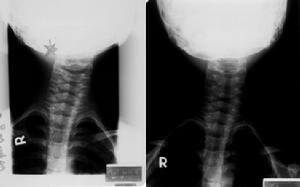

痙攣性斜頸根據病人發作情況較易確診,但應與以下疾病鑑別。

1.癔病性斜頸有致病的精神因素,發作突然,頭部及頸部活動變化多端,無一定規律,經暗示後,症狀可隨情緒穩定而緩解。

2.繼發性神經性斜頸頸椎腫瘤、損傷、骨關節炎、頸椎結核等可導致本病。頸椎間盤突出、枕大神經炎等,因頸部神經及肌肉受刺激,導致強直性斜頸。一側半規管受刺激引起的迷路性斜頸、先天性眼肌平衡障礙引起的眼性斜頸、先天性頸椎畸形引起的骨性斜頸、先天性胸鎖乳突肌攣縮及小腦第四腦室腫瘤早期所引起的斜頸等,均無陣攣作為鑑別,需進一步檢查發病原因。